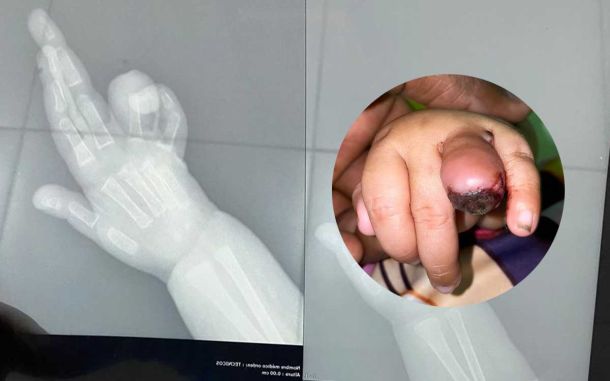

Mujer denuncia médicos del hospital Taiwan cortaron dedo de su niña al nacer

Una mujer denunció que dio a luz con cesárea en el Hospital Taiwan de Azua y cuando le entregaron a la criatura tenía su dedito “mochado” por la mitad y el personal médico le dijo que nació en esas condiciones.

La madre de la niña identificada como Dominga Ramírez, relató que “cuando recibió la bebé, su dedito estaba sangrando mucho y que la pediatra “cogió miedo”, tomó la criatura y se quedó con ella dos días”.

Asimismo, sostuvo que el personal sanitario no se hizo cargo, le dijeron “que la llevara al Hospital Pediátrico Robert Reid Cabral “Angelita”, que eso no “era nada”, lo…